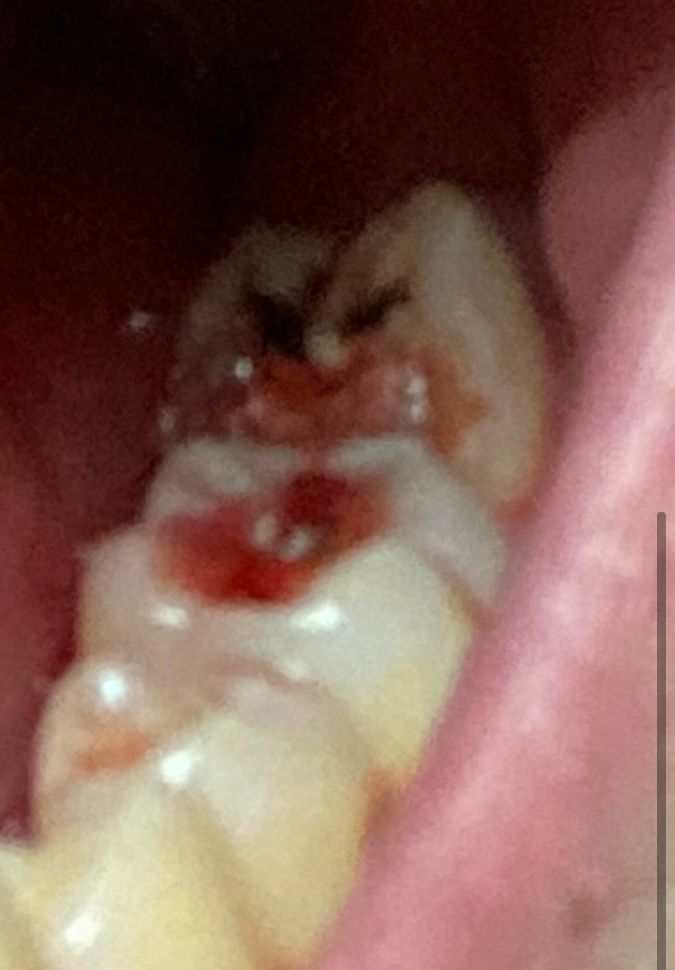

제 지인이 몇년전부터 치아가 안좋은것 같아보였는데 병원 안가고 버티더니 며칠 전부터는 어금니에 통증을 느껴서 병원을 가봐야하나 하더니 괜찮아졌다고 결국 안갔는데 오늘 밥먹다가 아프던 어금니 반정도 떨어져나가는 불상사가 일어났습니다 물마시면 치아가 시리고 거슬린다고 혓바닥으로 건드려서 피도 나는 상태인데요 일하는 시간이 길고 병원 갈 수 있는 시간이 적어서 휴무인 수요일이나 금요일에 병원에 가야할것같은데 이거 일상생활 해도 괜찮나요? 아니면 무리해서라도 월요일에 바로 병원진료 봐야할까요? (사진속 깨진 치아는 맨 뒤에 있는 어금니입니다)

사진이 흐려 정확하게 보이지는 않습니다.

사진이 정확히 보이진 않지만, 충치가 심하여 치아가 파절된것으로 보입니다.

치과는 응급 질환이 아니기 때문에 통증만 조절된다면 월요일날 바로 방문하지 않아도 되나 현재 정도의 증상이나 첨부해주신 사진 자료로 보았을 때 빠른 시일내로 치과를 방문하여 치료하는 것이 좋아 보입니다. 다수의 출혈 뿐만 아니라 충치범위가 매우 넓어 신경치료를 시도하지 못하고 바로 발치를 해야할 수도 있어 보입니다. 따라서 적극적인 치료가 필요해보입니다.